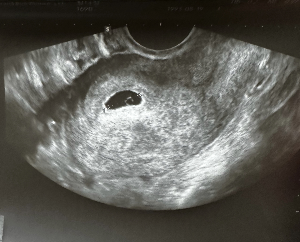

자궁외 임신의 진단은 여러 검사를 통해 종합적으로 이루어집니다. 먼저 혈액 검사를 통해 임신 호르몬 수치를 확인하며 정상 임신에서는 일정한 속도로 증가하는 특징이 있습니다. 그러나 자궁외 임신의 경우 호르몬 수치의 증가가 비정상적일 수 있습니다. 또한 프로게스테론 수치를 함께 확인하여 임신 상태를 평가할 수 있습니다. 초음파 검사를 통해 자궁 내 임신 여부를 확인하고 자궁 외 부위에 임신 조직이 존재하는지 확인합니다. 필요에 따라 복강경 검사를 시행하여 직접 확인하기도 합니다. 소파술을 통해 자궁 내 조직을 검사하여 자궁외 임신 여부를 판단하는 경우도 있습니다. 이러한 다양한 검사 방법을 통해 보다 정확한 진단이 가능합니다.